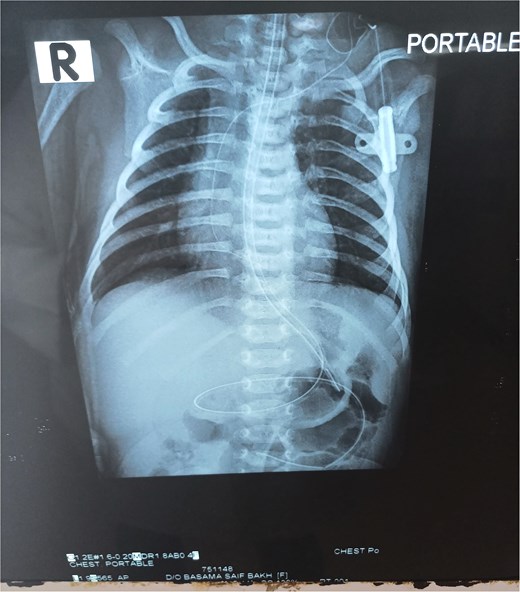

Chest X-ray was normal (Fig. 1). A water-soluble contrast meal was performed (Fig. 2) and the contrast arrested at the gastric antrum for 45 min. Then there was normal opacification of the duodenum and jejunum on follow-up films after 1.15 and 1.3 h. A complementary ultrasound (US) was done along with the contrast study and it showed a thick mucosal fold (4 mm) at the gastric antrum situated 1 cm away and on the left side of the duodenum. The pyloric canal was open and patent and had a normal wall thickness (1.5 mm) excluding hypertrophic pyloric stenosis.